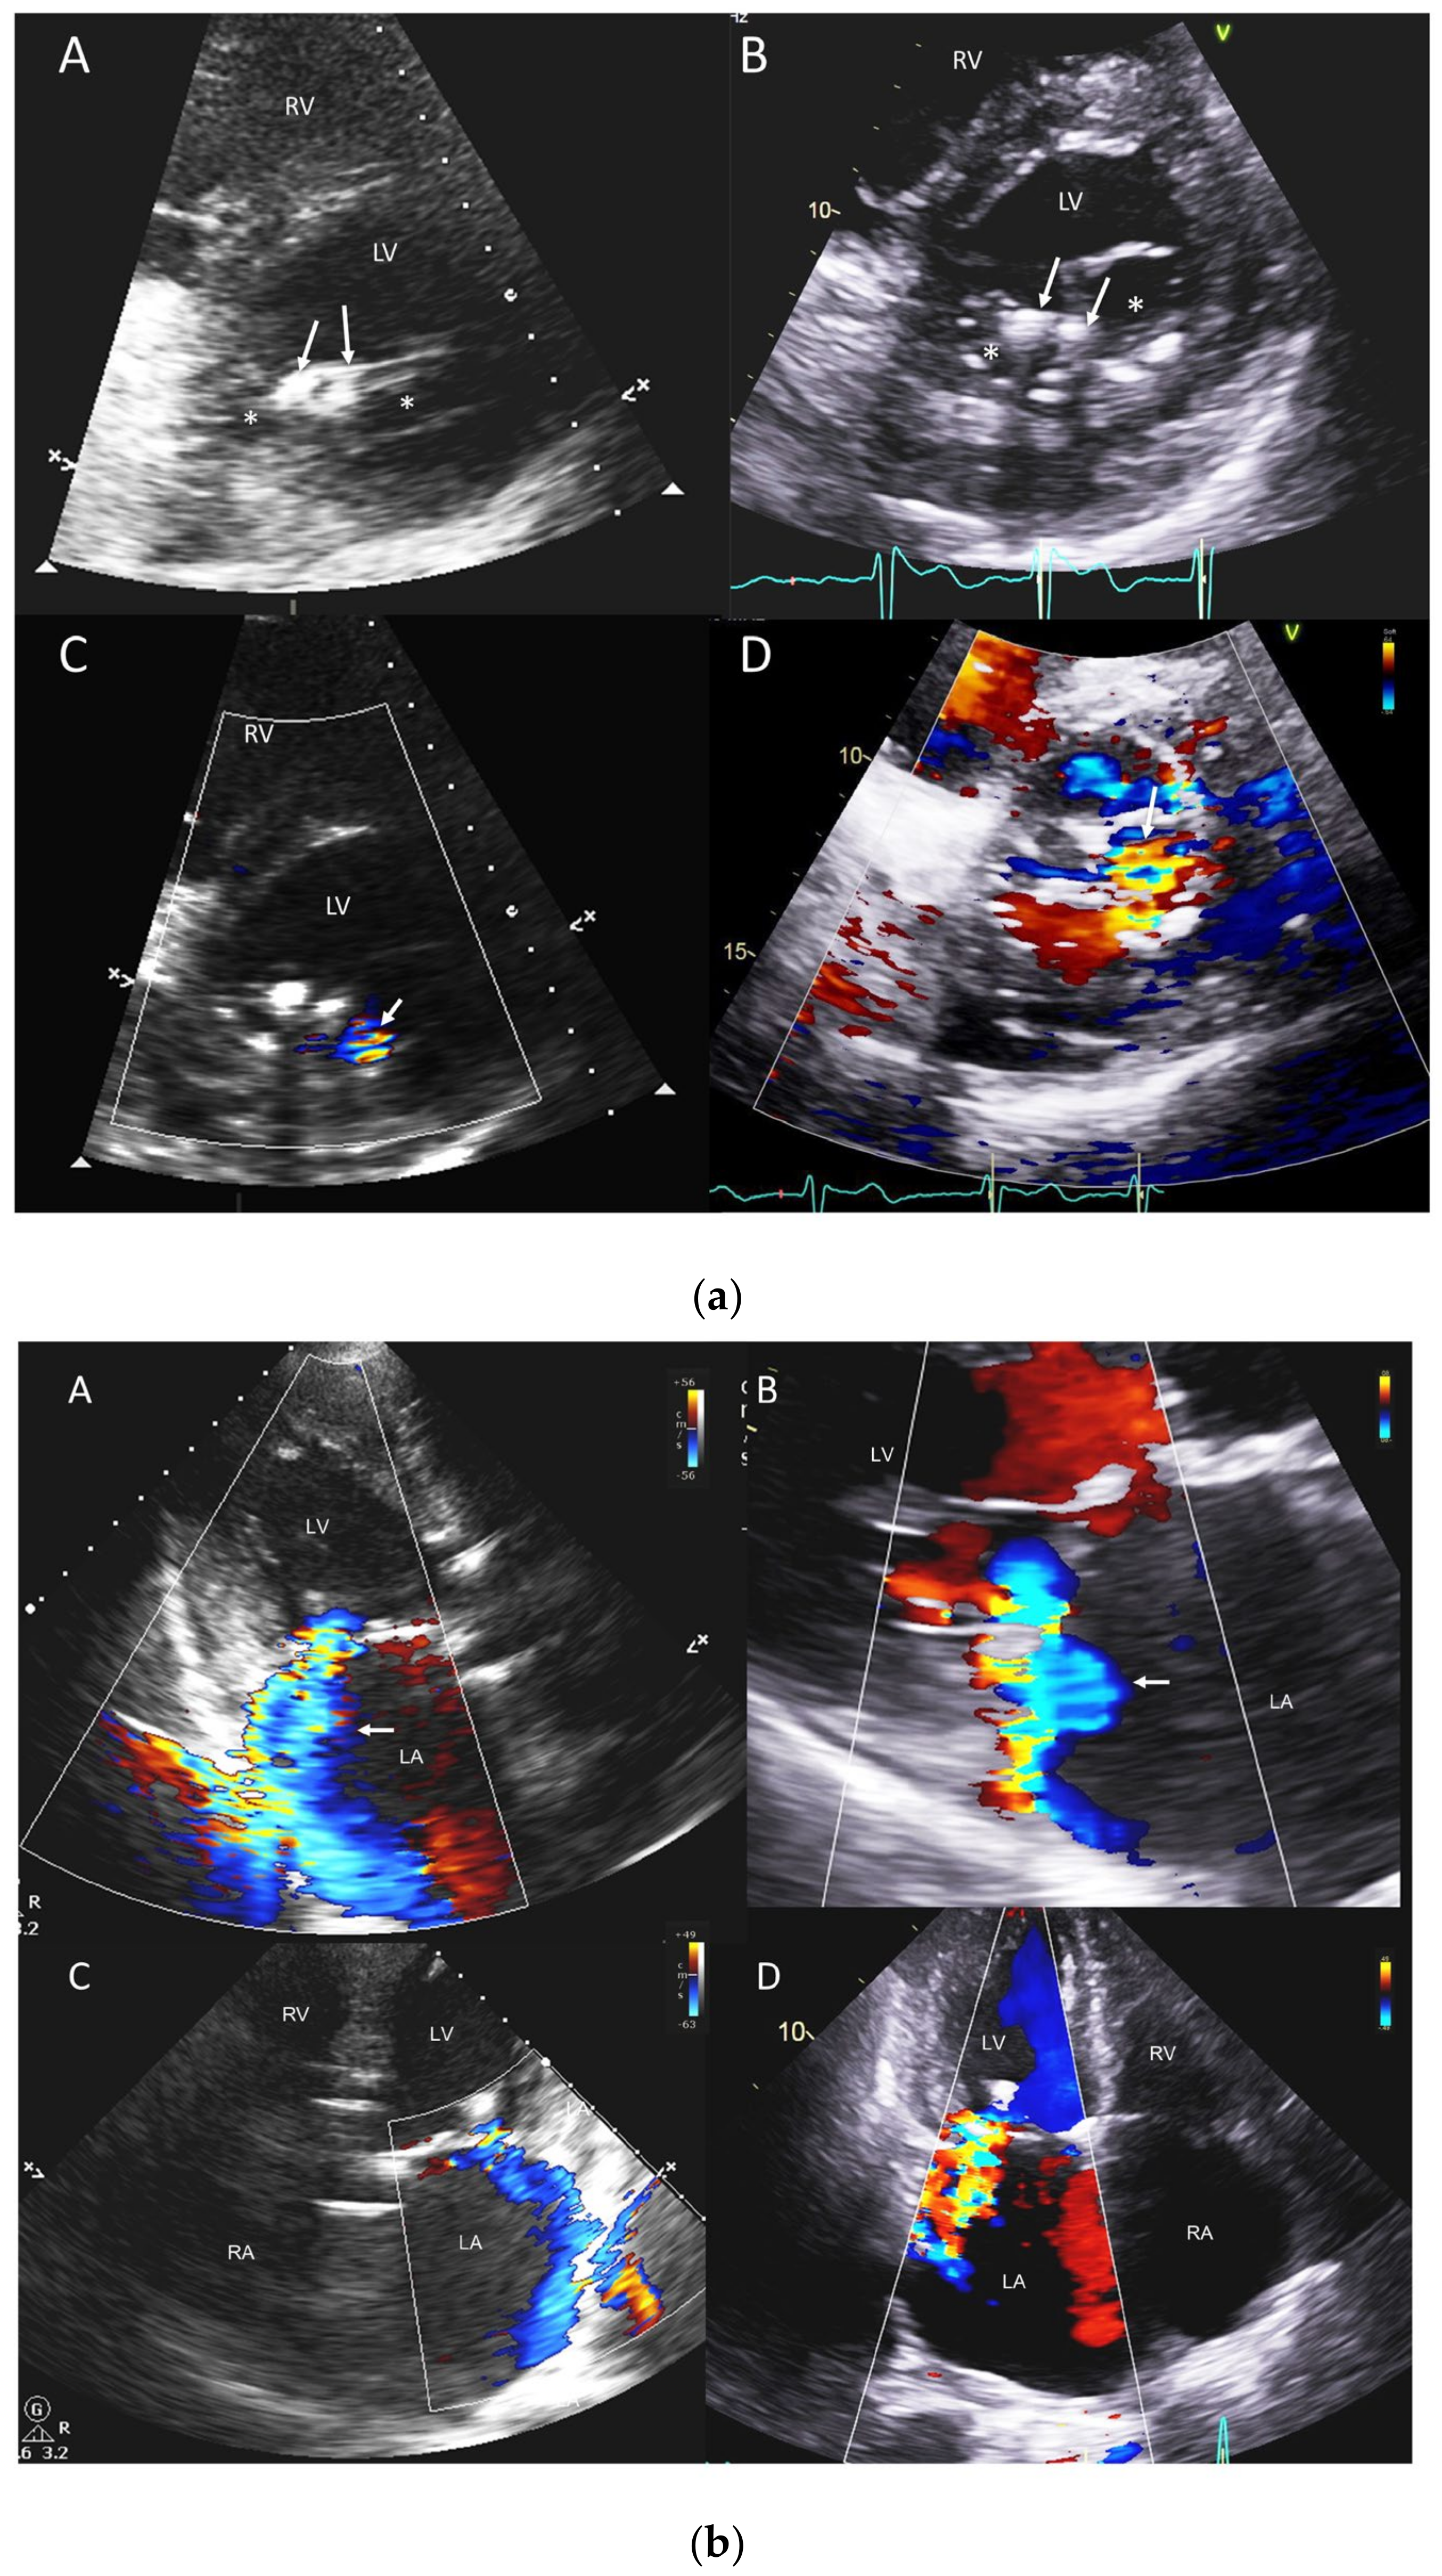

3.2. ≥Moderate Valvular Regurgitation

| Mitral regurgitation | 16 (20.8) | 17 (22.1) |

| Mitral stenosis | 1 (1.3) | 1 (1.3) |

| Aortic regurgitation | 10 (13.0) | 11 (14.3) |

| Aortic stenosis | 15 (19.5) | 18 (23.4) |

| Tricuspid regurgitation | 13 (16.9) | 14 (18.2) |